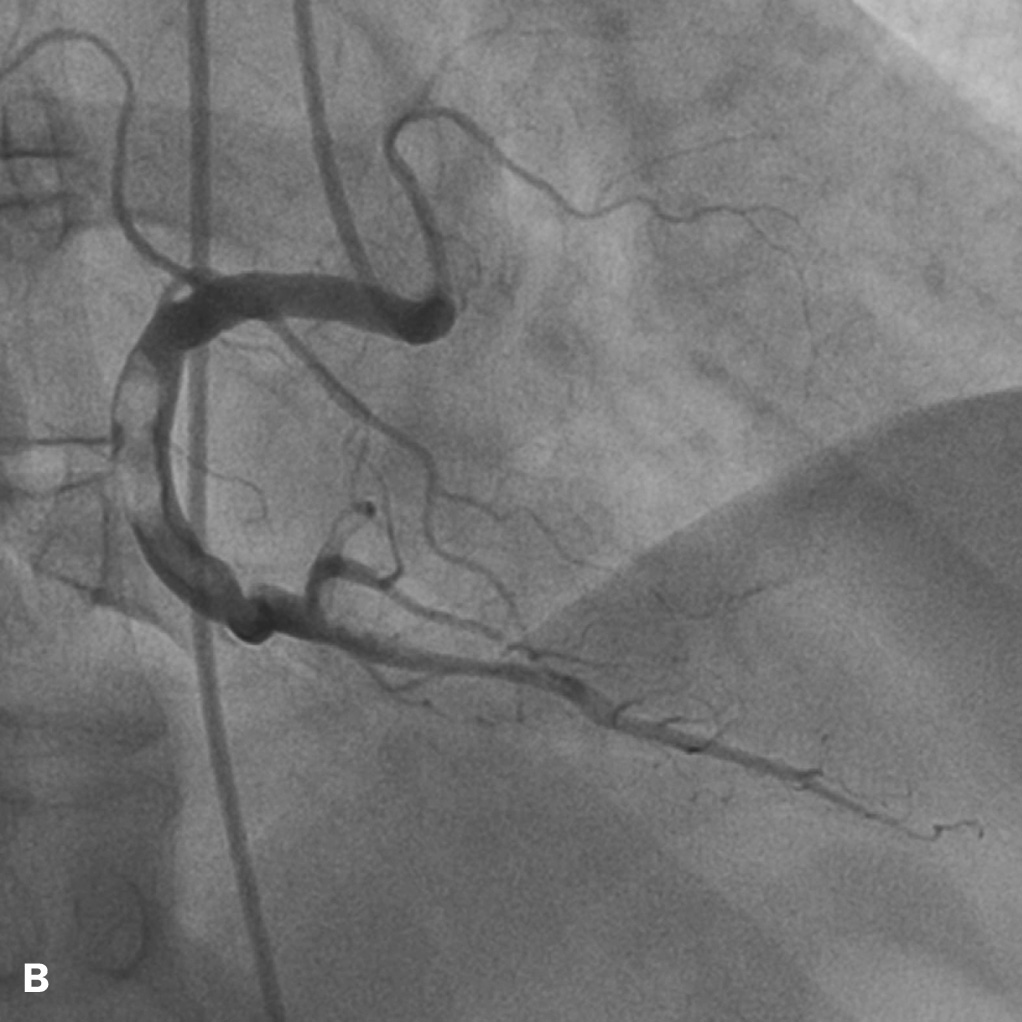

A 65-year-old man presented with a non-ST-elevation acute coronary syndrome. His medical history was unremarkable. Apart from a brother, who sustained a myocardial infarction at the age of 40, no cardiovascular risk factors were present. Coronary angiography revealed normal left anterior descending and circumflex arteries. The right coronary artery was subtotally occluded with an extensive thrombus running into the posterolateral branch (figures 1A and B). Despite appropriate medical treatment, intermittent chest pain persisted. The patient underwent a percutaneous coronary intervention with mechanical removal of the thrombus by aspiration followed by balloon dilatation. During the 12 hours preceding this procedure a glycoprotein IIb/IIIa receptor antagonist was continuously infused, while aspirin, clopidogrel, and a low-molecular-weight heparin (LMWH) were also administered. The intervention was only partially successful with limited restoration of right coronary perfusion resulting in a TIMII flow. Following the procedure, intermittent chest pain persisted initially but subsided after a few days of continued administration of aspirin, clopidogrel and an LMWH.